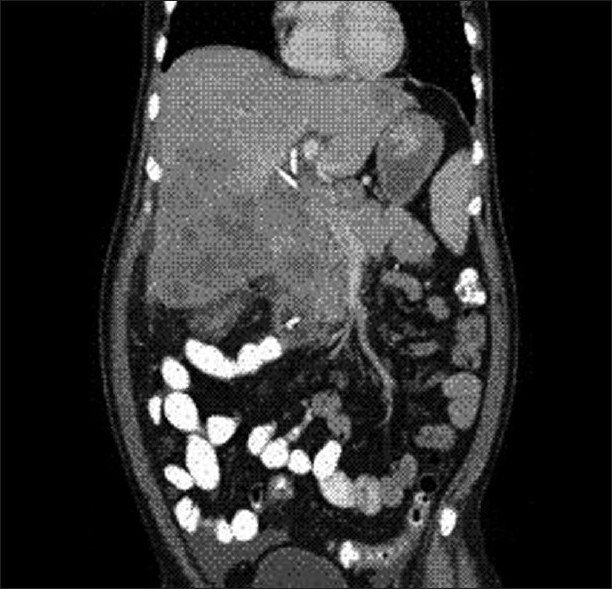

Physical examination revealed severe icterus and liver enlargement up to 5 cm below the right costal margin. The liver was hard and nontender. Ultrasonography (USG) and computed tomography (CT scan) revealed a large right and caudate lobe liver mass involving the gallbladder and common bile duct, with intrahepatic biliary radical (IHBR) dilatation, favoring the diagnosis of carcinoma gall-bladder with liver metastasis [Figures [Figures11 and and22].

| Figure 1 CT abdomen (coronal section) showing a large caudate lobe liver mass involving the gall bladder and common bile duct at porta with intrahepatic biliary radical (IHBR) dilatation